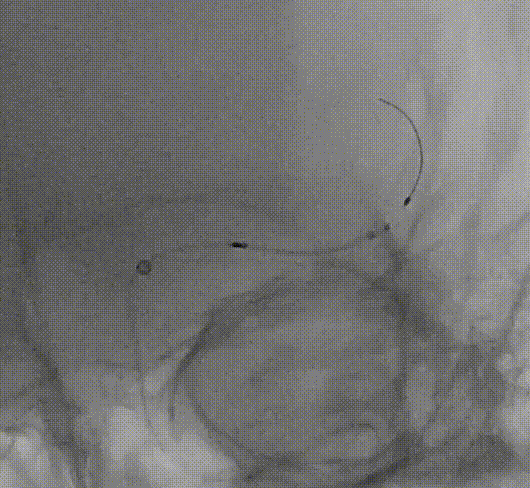

微导管通过后,结合首过效应、支架释放效应等决定取栓及后续策略。

6F 90cm Neuromax

6F 125cm 中天远端通路导管

Rebar-18微导管

200cm Synchro II微导丝

4-40 心玮取栓支架

微导丝前行有阻力,调整后通过

微导管通过后回撤

首过效应(+)

心玮 4-40取栓支架释放后,支架释放效应(+)

SWIM一把通?

管壁毛糙,泵替罗非班观察15分钟(60Kg,静脉推注7ml后7ml/h微泵维持)。

支架导管确认真腔

静脉维持基础上3ml替罗非班动脉推注,4.5*20 EZ(手头无EP)

支架输送导丝,路途显示残留狭窄,跟进支架导管备后扩

3m导丝支架内成袢通过

导丝到位后即刻造影

观察后血流变差

2.0*10白驹跟进困难,更换1.5*15

10atm扩张,血流维持差

2.0*10白驹通过顺利

打起后原位维持2分钟

“天又亮了”